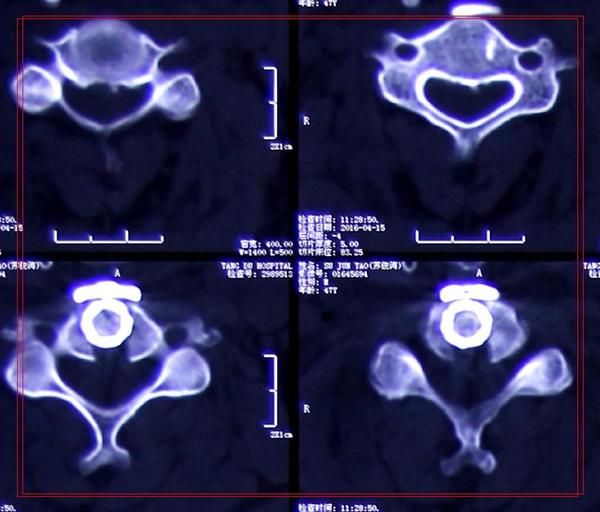

影像学资料